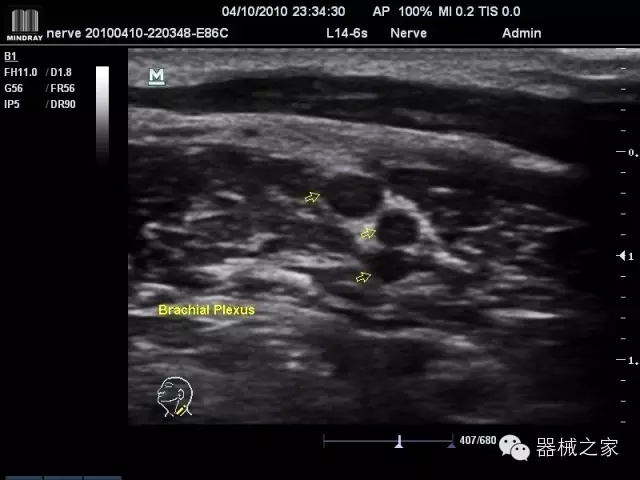

臨床圖片賞析

產(chǎn)品特點(diǎn)

·優(yōu)秀的圖像效果、強(qiáng)大的功能體驗(yàn)、豐富的探頭選擇、合理的便攜式設(shè)計(jì),全中文顯示及病人管理界面,使得M7在任何場合、任何時(shí)候都能快速響應(yīng)更好的心血管、腹部、婦產(chǎn)、小器官等常規(guī)超聲檢查以及肌骨、神經(jīng)、顱腦、術(shù)中等新興領(lǐng)域的使用需求;